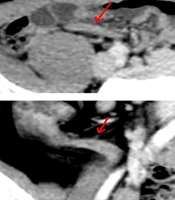

Abnormal appendix enhancement was defined as a difference in enhancement between the appendix and the cecal or ileal wall. Abnormal appendix content was defined as the presence of intraluminal fluid (Figure 1) or appendicoliths, rather than intraluminal air, within the appendix. Appendix erection was defined as the presence of an I-shaped or C-shaped appendix rather than a V-shaped, O-shaped, or S-shaped flaccid appendix on axial, sagittal, and coronal CT images. An I-shaped appendix was characterized by a straight or nearly straight appearance, while a C-shaped appendix was characterized by a curved, bow-like appearance (Figure 1). A V-shaped appendix had an acute angle at its turn, an O-shaped appendix appeared with the tip close to the opening, resembling a "kissing" posture, and an S-shaped appendix had a biconcave appearance (Figure 2).

Image appearance of an erected appendix: A and B, a 21-year-old male patient with appendicitis. Post contrast computed tomography (CT) on axial view showed an erected “I shape” appendix (red arrows). The appendix diameter was 6.6 mm. Note also the appendix had abnormal wall enhancement and filled with fluid; C and D, a 62-year-old male patient with appendicitis. Post contrast CT on coronal view showed an erected “C shape” appendix (red arrows) with abnormal wall enhancement and intraluminal fluid. Appendix diameter was 8 mm.